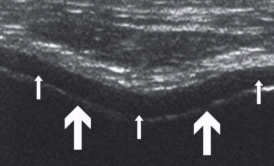

Appearance of muscles on US

LAX

Homogeneous with multiple parallel echoes

“Feather” appearance - striated pennate appearance

Hypoechoic muscle fibers arranged in columns interspersed by hyperechoic fibroadipose tissue

SAX

Homogeneous with punctuate echoes